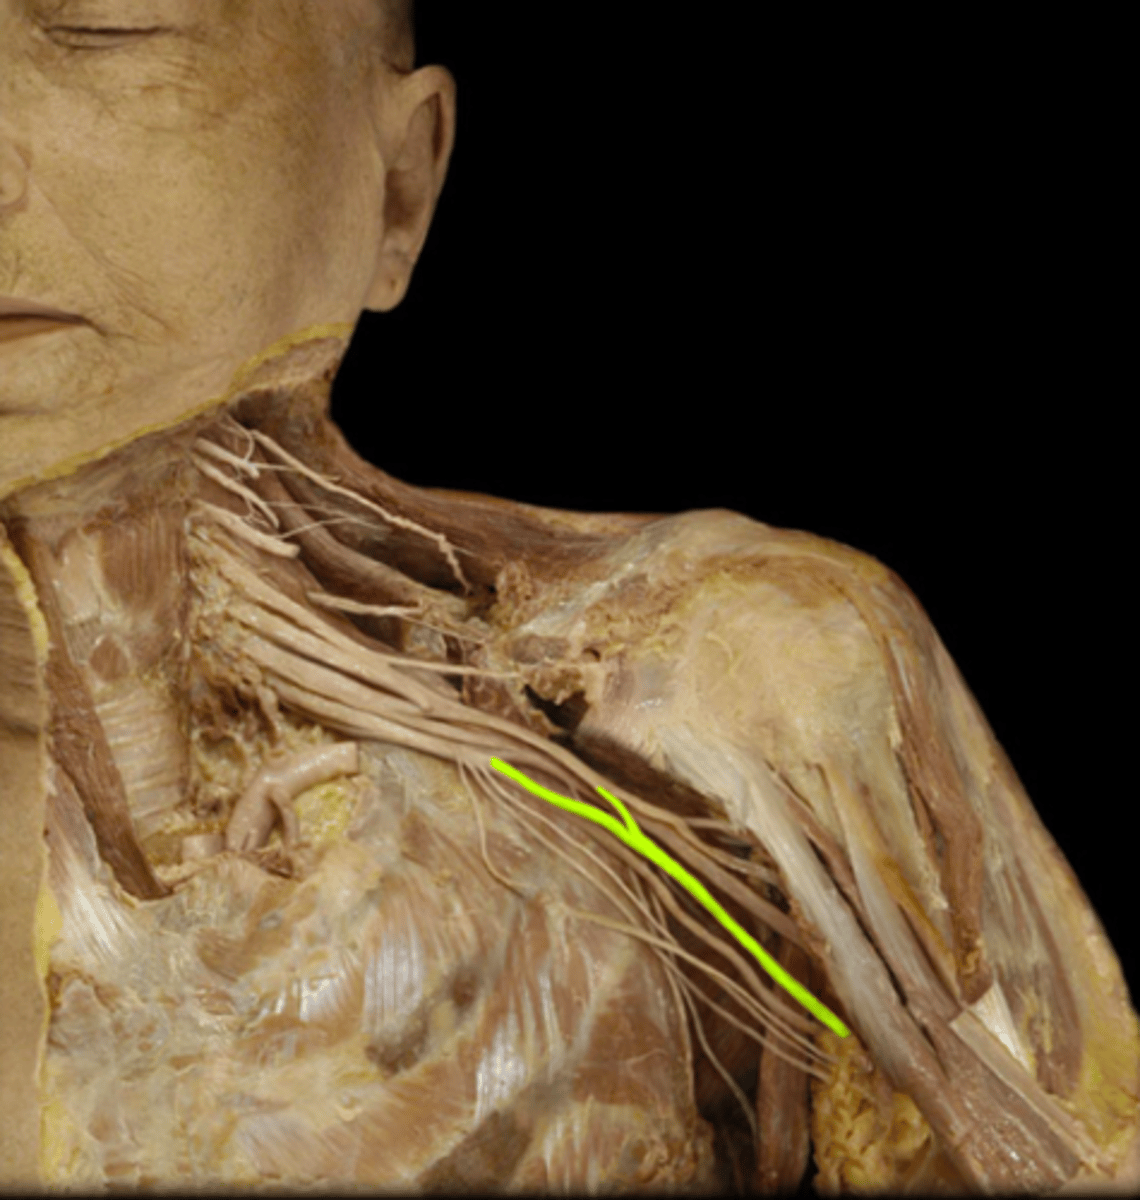

Spine of scapula

Name the structure.